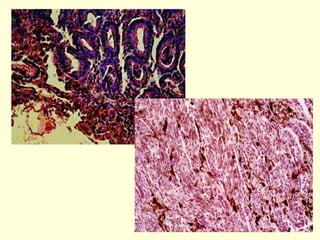

Klinik - S. Spinozum

• Yassı      Hücreli    Karsinom:       Bazal     hücreli

karsinomdan sonra en sık görülen ikinci deri kanseri

çeşididir. Çevre       dokulara    metastaz     yapar.

Muhtemelen X – ışını, mor ötesi radyasyonu ve

arsenik gibi çeşitli kimyasal maddelerin de

aralarında yer aldığı çevresel unsurların tetikleyici

etkisiyle ortaya çıkmaktadır. Spinoz tabakadaki

hücrelerden kaynaklanır. Sıklıkla kanamalarla

seyreden ve alttaki dokulara yayılan hiperkeratoz

plakları şeklinde görülür. Tedavisi cerrahidir.